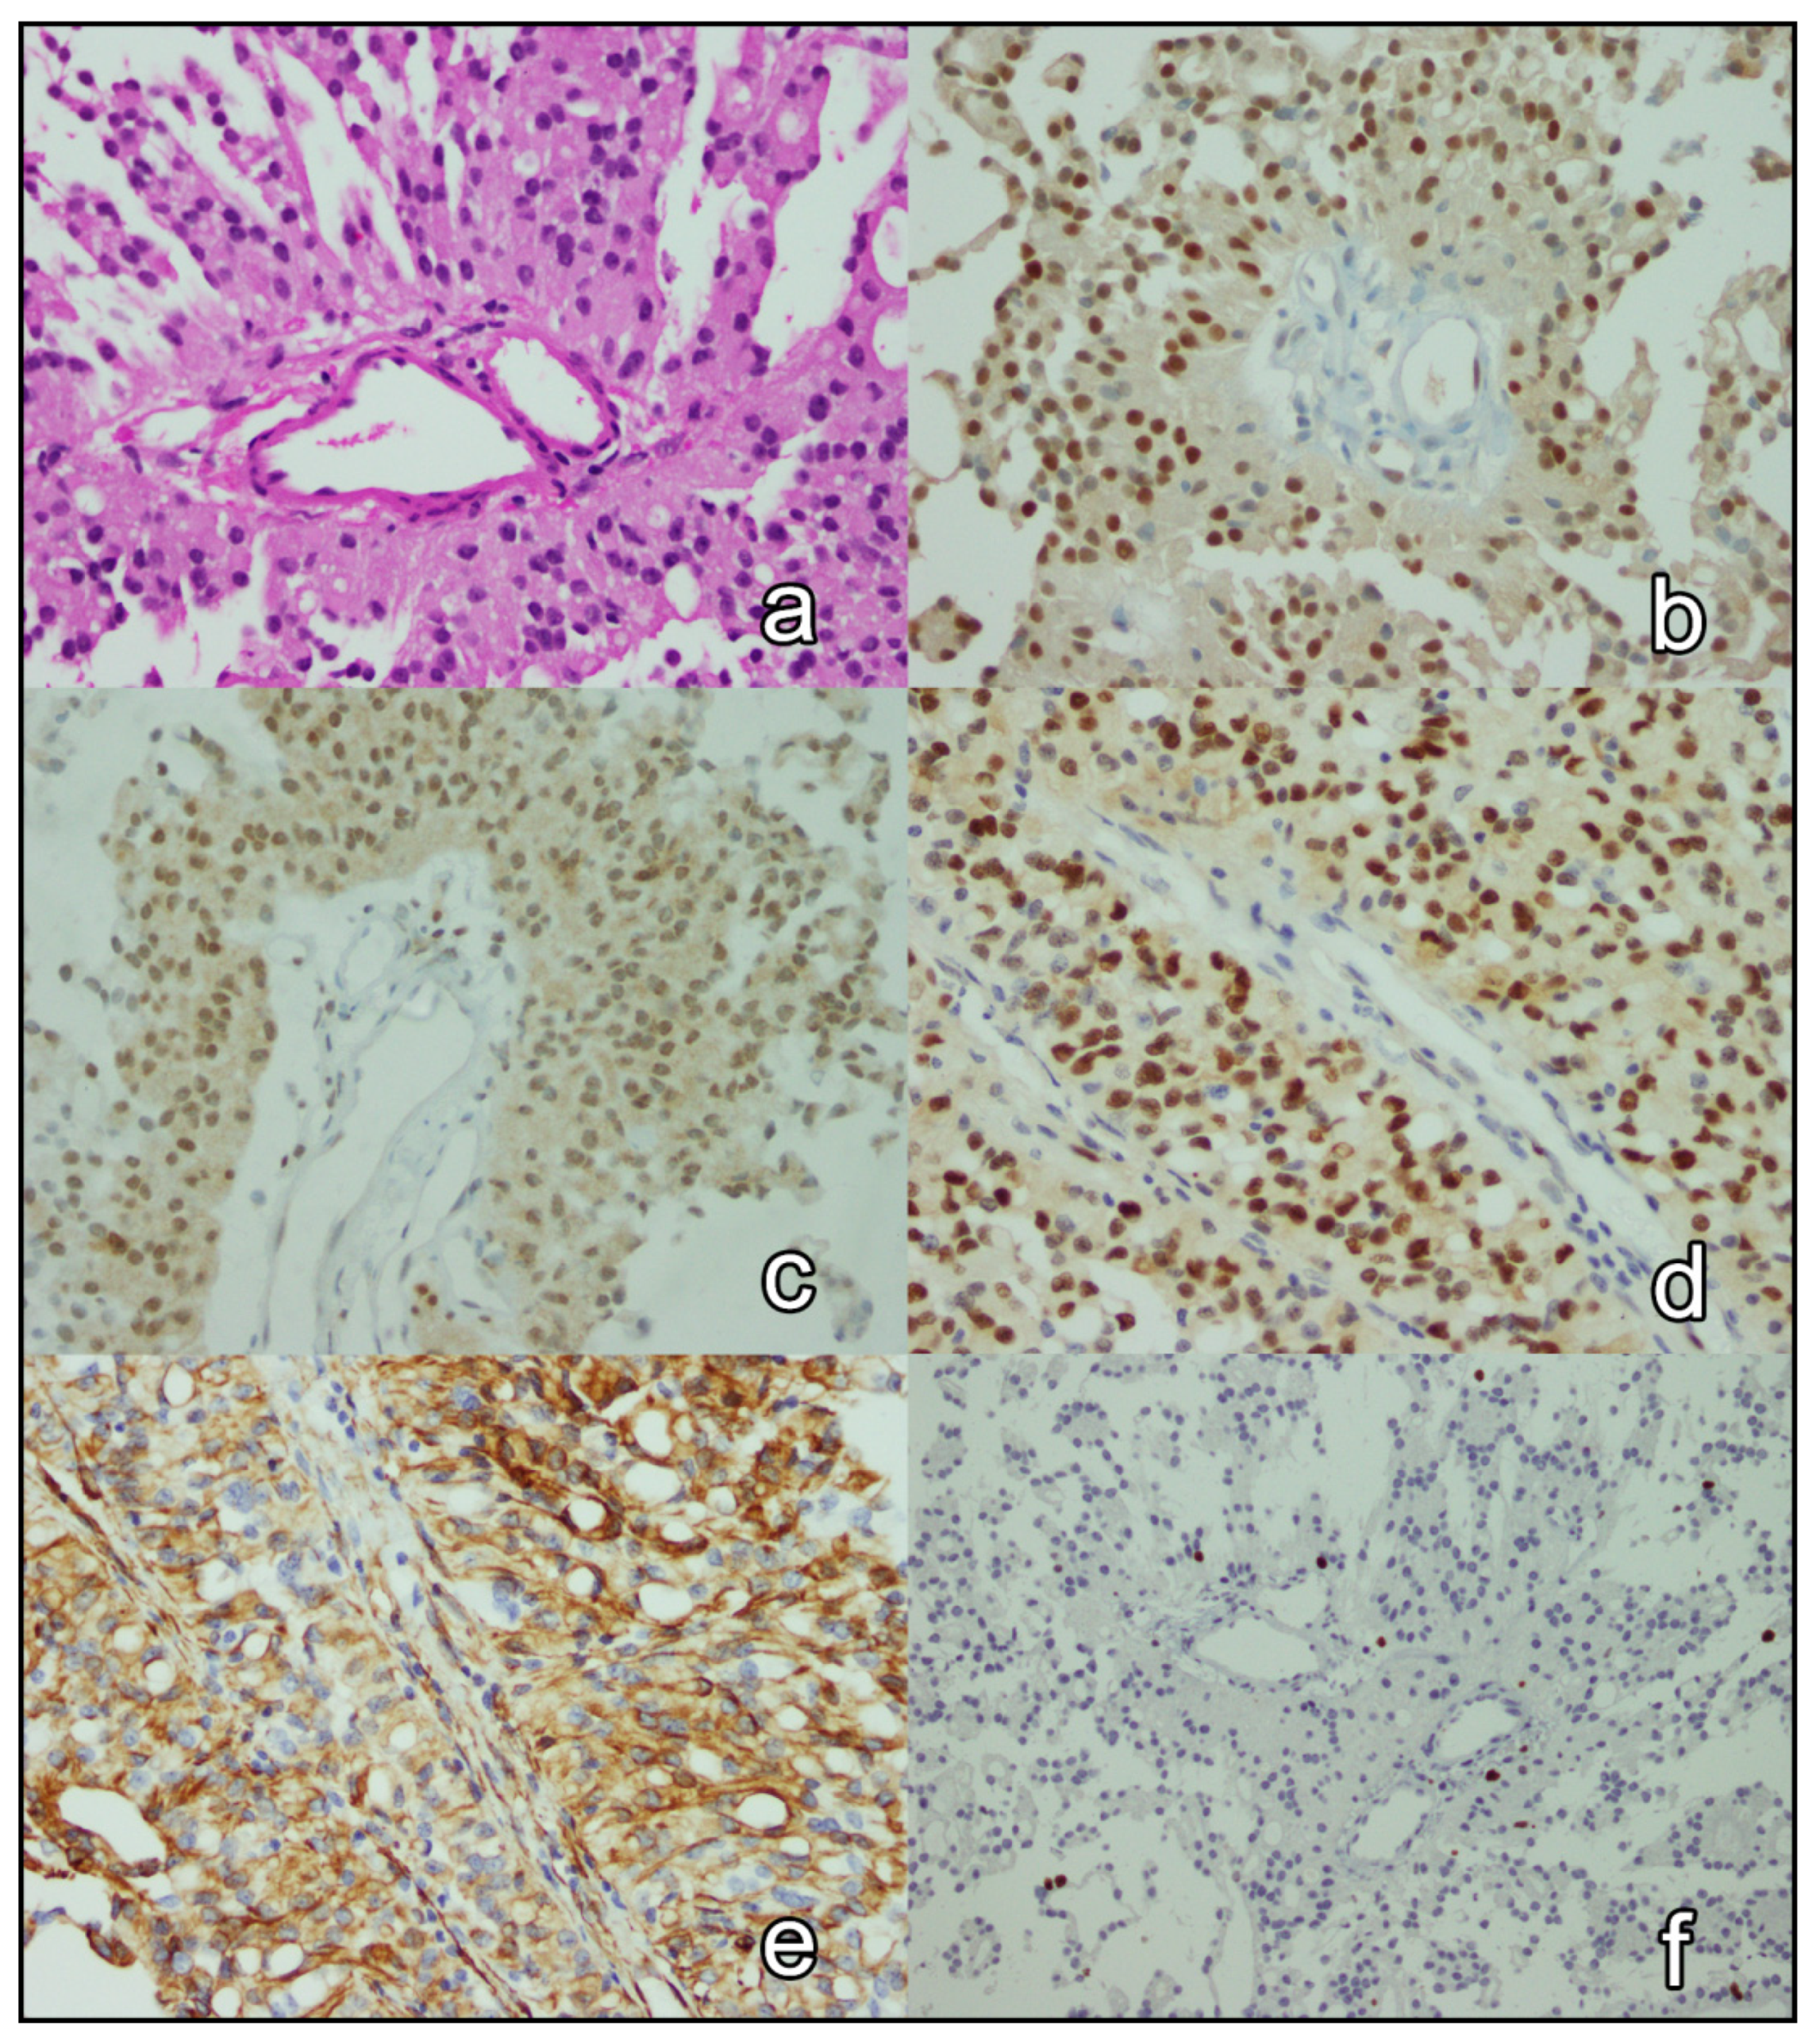

3.3. Immunohistochemical Analysis